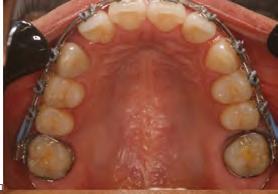

en paciente adulto tratado con extracciones de primeros molares permanentes. Reporte de caso

Dentista y Paciente 52 Sonriendo al futuro